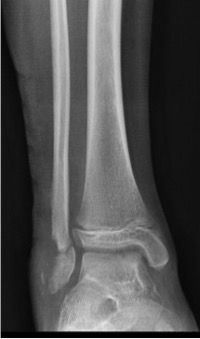

Fracturas fisarias Salter-Harris VI de tobillo y pie. [Salter-Harris VI fractures of the foot and ankle.]